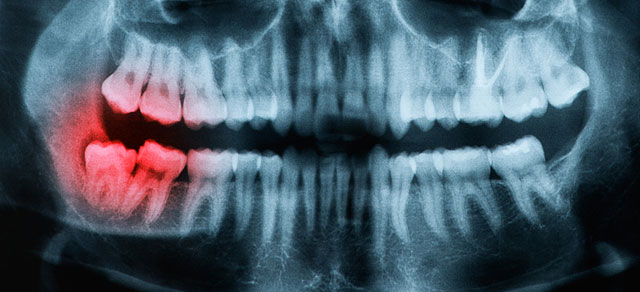

Impacted Teeth require oral surgery. Wisdom teeth, otherwise known as third molars, are the last set of teeth to develop. Sometimes these teeth emerge from the gum line and the jaw is large enough to allow room for them, but most of the time, this is not the case. More often, one or more of these third molars fails to emerge in proper alignment or fails to fully emerge through the gum line and becomes entrapped or "impacted" between the jawbone and the gum tissue. Impacted wisdom teeth can result in swelling, pain, and infection of the gum tissue surrounding the wisdom teeth. In addition, impacted wisdom teeth can cause permanent damage to nearby teeth, gums, and bone and can sometimes lead to the formation of cysts or tumors that can destroy sections of the jaw. Therefore, dentists recommend people with impacted wisdom teeth have them surgically removed.